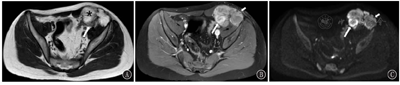

在MRI上,2例病灶周围呈T1WI及T2WI等信号,中心呈斑片样或结节样T1WI及T2WI高信号(图3),1例病变T1WI上呈周围等信号,中心高信号,T2WI上呈周围高信号,中心更高信号。弥散加权成像(DWI)(b=800 s/mm2)上病灶周边部分呈高信号且增强后强化明显,中心部分弥散不受限,增强后不强化或仅轻微强化(图4)。3例病变内均观察到迂曲流空血管影。1例腹壁及右髂窝多发结节灶(图5)、1例腹股沟区多发肿大淋巴结亦可见弥散受限及明显较均匀强化。

在MRI平扫图像上,本组肿瘤多数呈现出"内高外低"的信号特点:即T1WI上多数表现为中心高信号、周围等信号,T2WI上病灶周围呈等/高信号,中心呈高/更高信号,这可能与肿瘤中心部位的出血、坏死有关。高b值DWI上可见病灶周边部分弥散受限且增强后强化明显,中心部分弥散不受限,增强后不强化或仅轻微强化,这种"弥散与强化相对应"的表现可能提示肿瘤的外周部分肿瘤细胞排列密集或具有恶性潜能。1例腹壁及右髂窝多发结节灶、1例腹股沟区多发肿大淋巴结亦可见弥散受限及明显较均匀强化,提示为恶性转移。3例病变内均观察到迂曲流空血管影,多以周围分布为主。